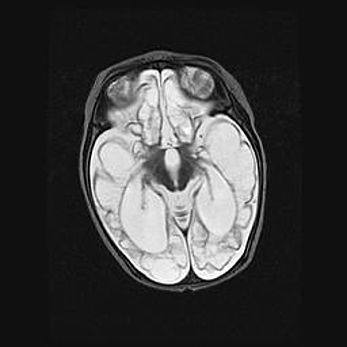

Мальформация Денди-Уокера. Киста задней черепной ямки.

Агенезия мозолистого тела.

Возраст: 2,5 месяца

Вес: 2420 г

Пол: женский

Окружность головы: 37 см

Срок гестации: 32 недели

Мальформация Денди—Уокера — редкий вид патологии ЦНС, представляющий собой врожденный порок развития каудального отдела ствола и червя мозжечка, ведущий к неполному раскрытию срединной (Мажанди) и латеральных (Лушка) апертур IV желудочка мозга. Для этогно синдрома характерна триада симптомов: гипотрофия червя мозжечка и/или полушарий мозжечка, кисты задней черепной ямки, гидроцефалия различной степени. В 70% случаев порок сочетается и с другими аномалиями головного мозга, в частности с агенезией мозолистого тела.